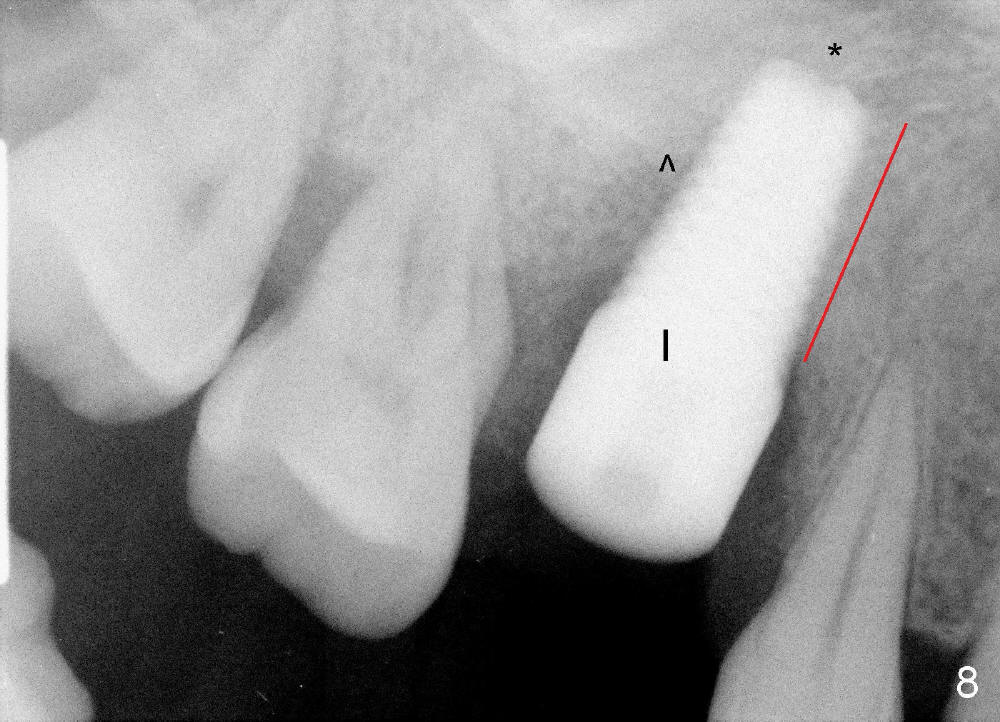

The tooth #3 has severe periodontitis with probably endodontic lesion (Fig.1,2). The patient is a 43-year-old man with apprehension of dentistry. An acute infection causes pain and tooth shift (Fig.4,5). A 7x17 mm immediate implant is planned (Fig.3). The palatal socket is shallow (Fig.6 P), corresponding to severe recessive palatal root (Fig.5 P). The osteotomy is created mainly in the buccal socket (Fig.6 B), exactly in the lingual slope of the septum. Initially osteotomes are used, followed by tap placement (Fig.7 T (4.5x20 mm at the depth of 17 mm). When the implant is placed as planned (Fig.8 I), there is more vertical contact (Fig.8 red line) than that associated with the tap (Fig.7 red line). The corresponding insertion torque is between 50 and 60 Ncm. There is only one small gap buccally, which is filled with bone graft (Fig.9 <). After the insertion of a short abutments with vertical slots (Fig.9,10 A), perio dressing is used to cover the wound. The palatal socket is expected to heal uneventfully (Fig.10 P). In fact, it does in 7 days (Fig.12 P); the bone graft in the mesiobuccal aspect is healing and stabilized (Fig.11 <). By two weeks postop, the mesiobuccal socket has healed (Fig.13 <). With removal of a diseased tooth, our body has amazing power to heal.